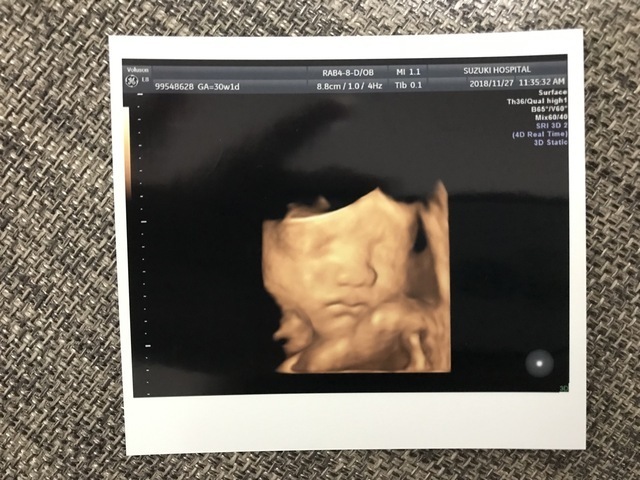

35週0日(35w0d・男の子)|nsa さん(37歳)

エコー写真撮影時のエピソード:

今までパパが見ていた時は、お鼻しかみせなかったのが、今回目も鼻も口もわかり、手で顔を隠してます!エコー動画では、寝てるのに口をパクパクしていて、3か月入院しているので、子供への実感がすごくわかったみたいです。食事は、制限が無いので、食べれる物をたべてます。